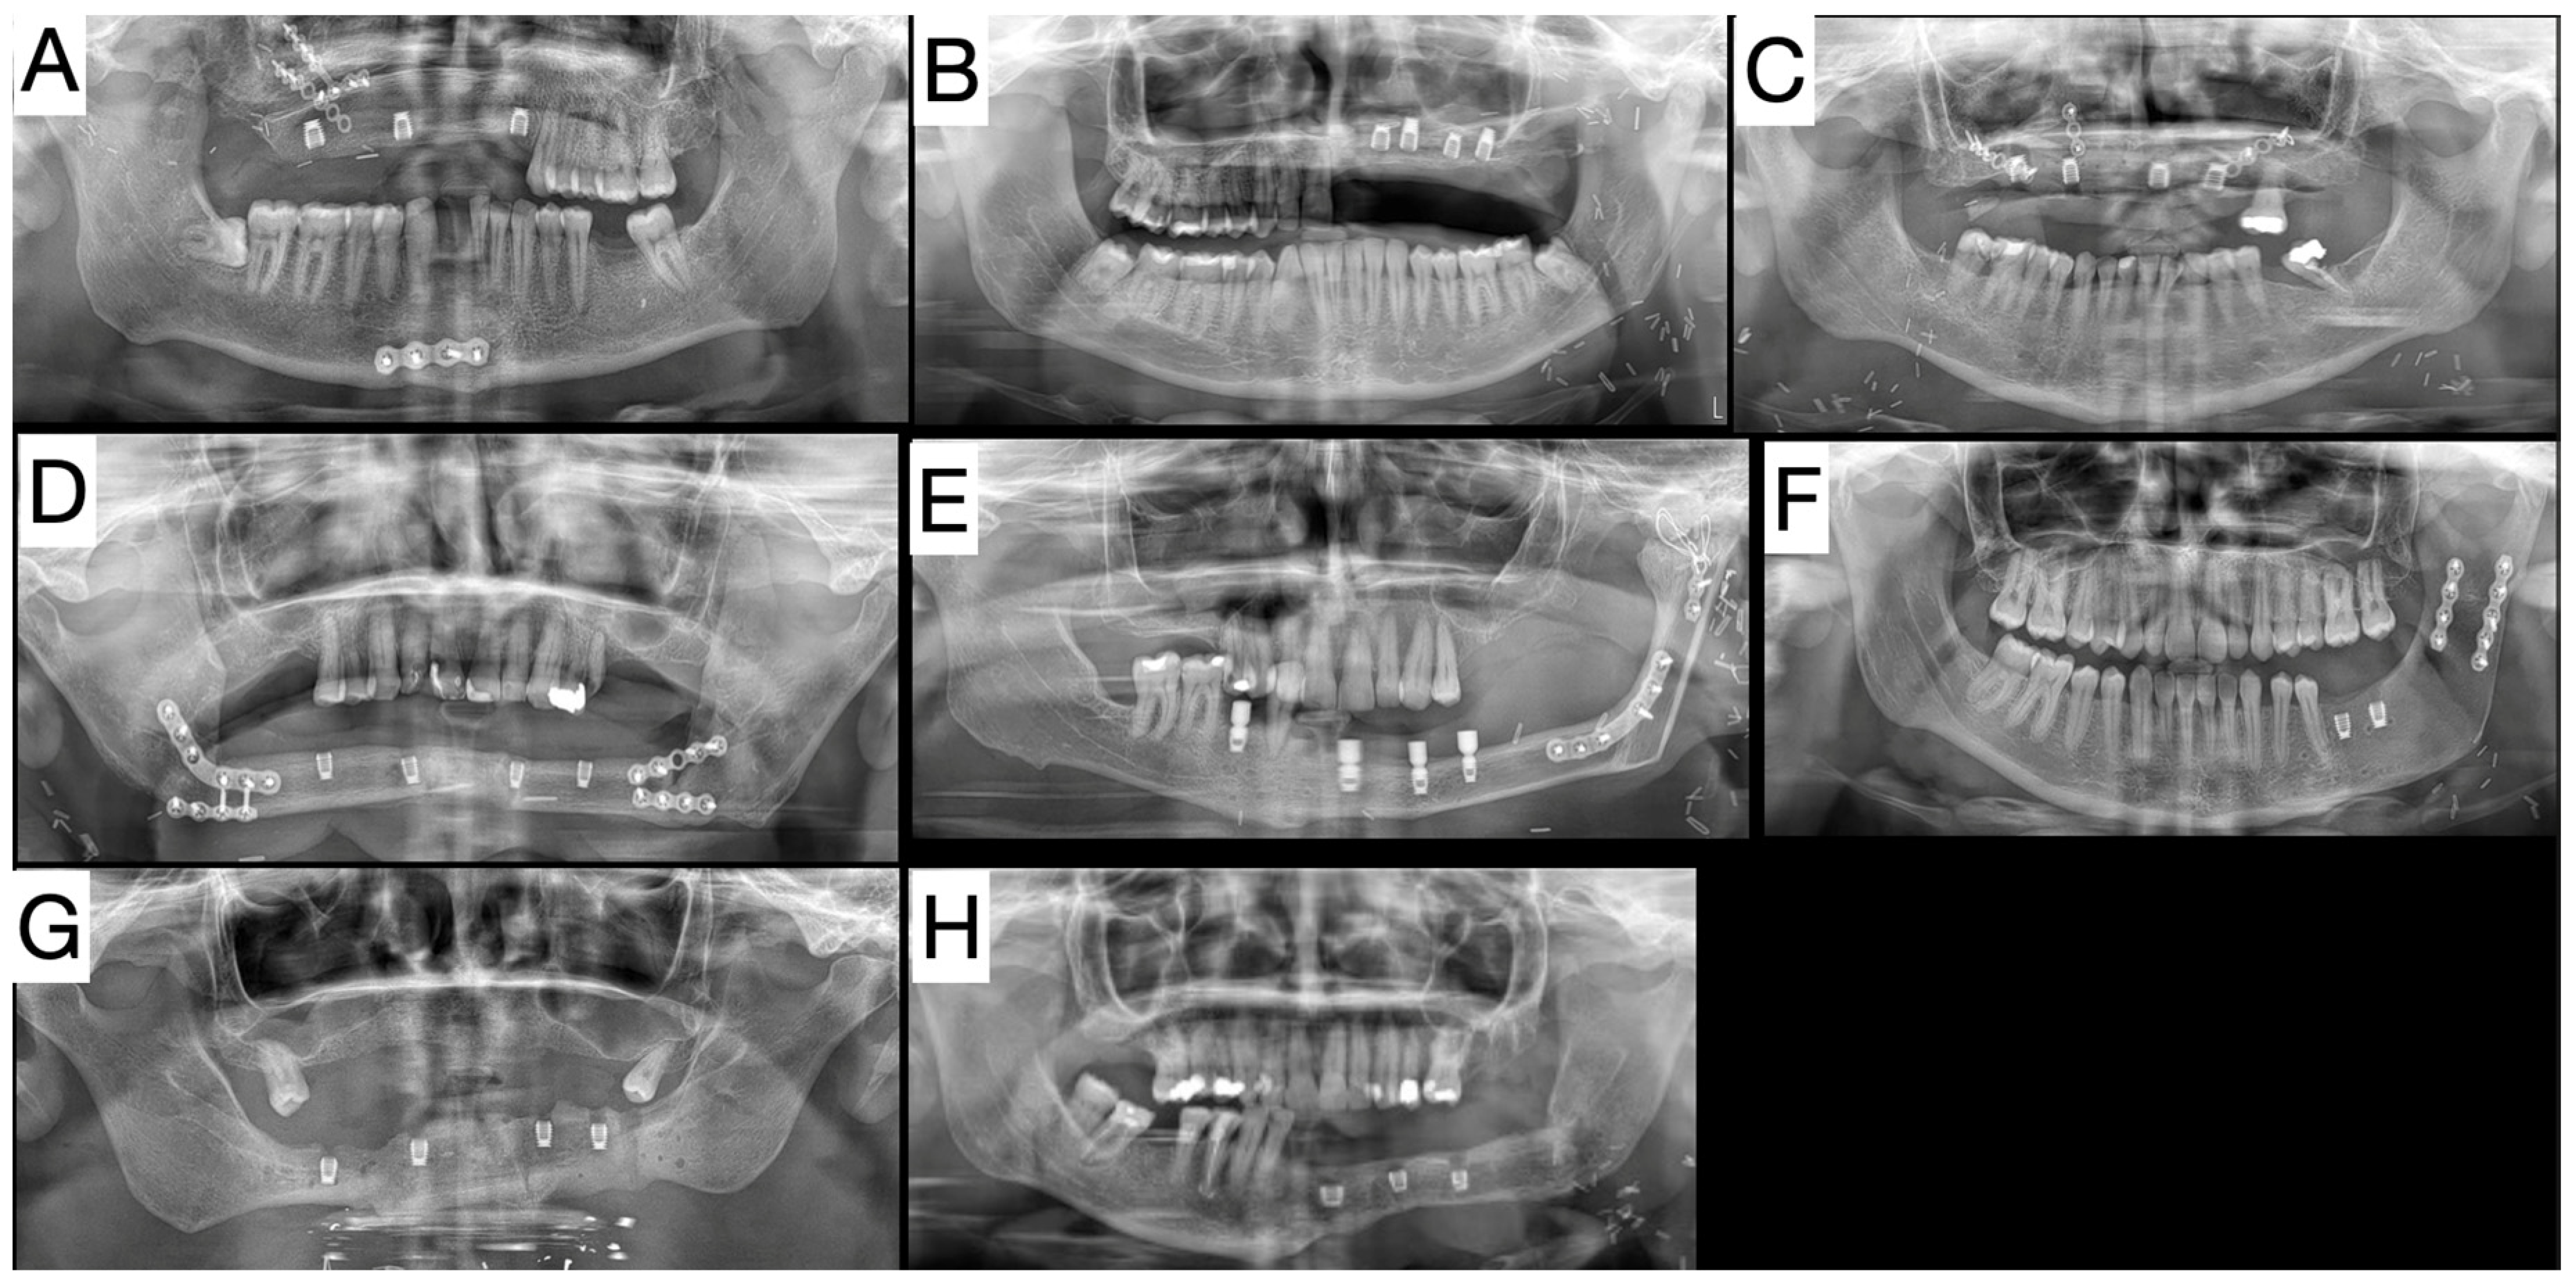

| Sex | Age at Time of Placing Dental Implants | Reconstructed Jaw | Type of Free Flap * | Number of Dental Implants in Free Flap | Implant Size (Bicon, Bicon LLC) | Status | |

|---|---|---|---|---|---|---|---|

| Patient No. 1 | Male | 67 | Mandible | FFF | 4 | 4.0 × 6.0 Integra CP | Prosthetic work in function |

| Patient No. 2 | Male | 51 | Mandible | FFF | 3 | 4.0 × 6.0 Integra CP | Adjusting prosthetic work |

| Patient No. 3 | Female | 55 | Maxilla | FFF | 4 | 4.0 × 6.5 Integra CP | Prosthetic work in function |

| Patient No. 4 | Male | 24 | Maxilla | FFF | 4 | 4.5 × 6.0 Integra CP (2×) 4.5 × 8.0 Integra CP (2×) | Prosthetic work in function |

| Patient No. 5 | Male | 26 | Maxilla | DCIA | 3 | 4.5 × 6.0 Integra CP (1×) 5.0 × 6.0 Integra CP (2×) | Prosthetic work in function |

| Patient No. 6 | Female | 21 | Mandible | DCIA | 2 | 4.5 × 6.0 Integra CP (1×) 5.0 × 6.0 Integra CP (1×) | Prosthetic work in function |

| Patient No. 7 | Male | 46 | Mandible | FFF | 4 | 5.0 × 6.0 Integra CP (4×) | Adjusting prosthetic work |

| Patient No. 8 | Female | 55 | Mandible | FFF | 3 | 4.5 × 5.0 mm Integra-CP (3×) | Loaded interim fixed prostheses |